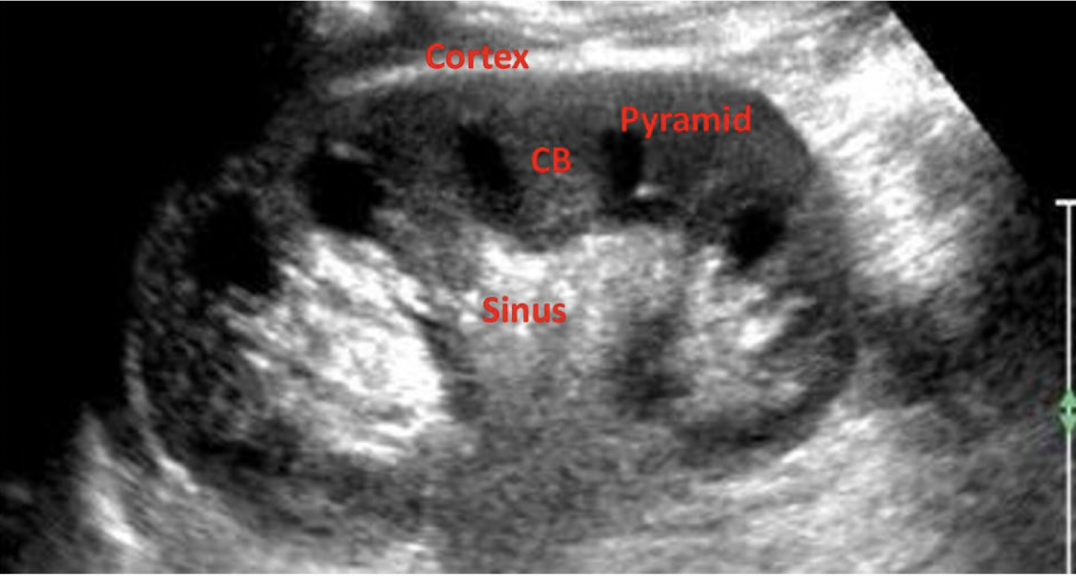

Review this image

What does CB stand for in this image?

Column of Bertin

Prominent Columns of Bertin can be mistaken for:

a renal mass